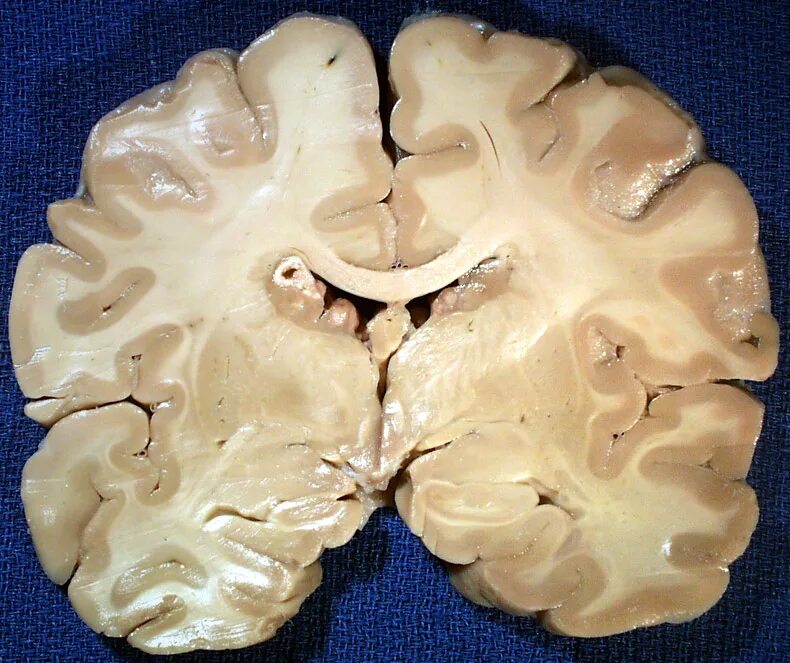

Туберкулезный склероз